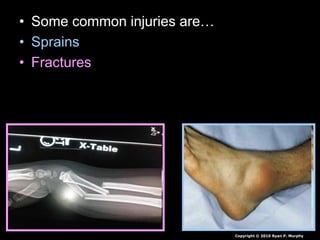

• Some common injuries are…

• Sprains

• Fractures

• Dislocations

• Which pictures goes with the correct term?

A break in the bone, made

of living tissue and repair

happens quickly.

An impact to the

skeleton can force a

bone out of its joint

Ligaments or tendons

get pulled or torn

beyond their range